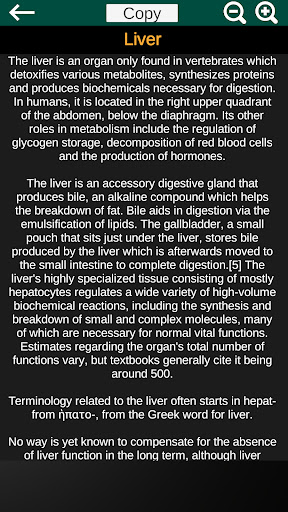

* Описи кожного органу.